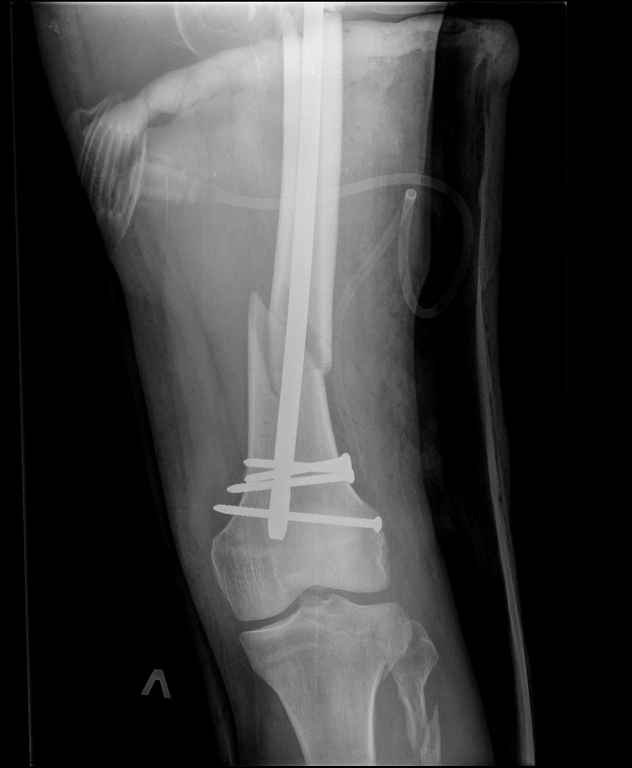

Ds: ТСТ. ЗЧМТ. СГМ. ЗТГК. О/фрагментарный перелом левого бедра. З/оскольчатый перелом с\3 левого плеча. Перелом левого локтевого отростка. З/перелом наружного мыщелка б/берцовой кости в/3 м/берцовой кости левой голени. при поступлении, ПХО раны левого бедра( рана 1х1см по наружной поверхности бедра в с/3) налажено скелетное вытяжение , и гипсовая лонгета на левую в/конечность. Находился в реанимации. 17.02.11 был прооперирован: БИОС левого плеча, о/синтез левого локтевого отростка по Веберу, БИОС левого бедра (длинная версия Fi-Can Sanatmetal диаметр 10мм), мыщелок голени трогать не стали.при остеосинтезе бедра возникли трудности при закрытй репозиции перелома в н/3, в связи с чем решили открыться внизу , отрепонировали без особого труда и выполнили блокирование во фронтальной плоскости 3-мя винтами + 1 винт спереди гвоздя (промазал). Убрал костодержатель, все нормально, контроль ЭОПом стояние отломков нормальное, зашились. На контрольной R-мме на утро выявлено вторичное смещение дистального отломка. Левая нога по сравнению со здоровой удлиннена до 2,5см( это за счет вальгусной установки гвоздя в проксимальном отделе, боялся свалиться на варус). Теперь думаем как поправить положение отломков в н/3, и зафиксировать так чтобы не съехало. Наше предложение расшиться в н/3 бедра, разблокироваться, перелом отрепонировать вновь и установить 1или 2отклоняющих винта в сагитальной плоскости, затем заблокироваться во фронтальной плоскости снова. Помогите советом, как выйти достойно из сложившейся ситуации. Заранее спасибо.

С моей точки зрения удлинение (если таковое имеется) произошло не за счёт вальгусной установки стержня. На контрольной рентгенограмме блокирующие винты точно расположены в шейке бедренной кости и в центре ротации головки. И даже если выбран стержень с максимальным из выпускаемых углом в 135 градусов, он не обеспечит столь значительного удлинения конечности. Увеличенный шеечно-диафизарный угол на контрольной рентгенограмме со стержнем объясняется наружной ротацией конечности при рентгенографии и возникающем при этом проекционном искажении ШДУ. Скорее всего, удлинение конечности объясняется наличием диастаза между отломками в вертельной области.

> - Убрал костодержатель, все нормально, контроль ЭОПом стояние отломков нормальное, зашились. На контрольной R-мме на утро выявлено вторичное смещение дистального отломка.

Важно установить из-за чего произошла вальгусная деформация дистального отломка (при условии, что на операционном столе после дистального блокирования её не было). Если взять в руки стержень и ввести в дистальное круглое отверстие блокирующий винт, то из-за разности в диаметрах блокирующего винта и диаметра блокирующего отверстия в стержне, возможно отклонение стержня во фронтальной плоскости до 13 градусов в каждую из сторон. Если второе отверстие для блокирования на дистальном конце стержня круглое, проблема «качания» дистального отломка во фронтальной плоскости на одном блокирующем винте при инфраистмальных переломах решается введением второго блокирующего винта во фронтальной плоскости. Если второе блокирующее отверстие овальное, введение второго блокирующего винта во фронтальной плоскости эту проблему не решит (кажется, это ваш случай). В таком случае лучшим решением является введение блокирующего винта в сагитальной плоскости через соответствующее отверстие стержня (это всегда лучший вариант). Однако в выбранном стержне такого отверстия нет. Поэтому мы бы поступили следующим образом. Удалили бы все дистальные блокирующие винты. Выполнили бы открытую репозицию дистального перелома на стержне с ликвидацией вальгусной деформации. Мне представляется, что это технически выполнимо, поскольку стержень не погружен в мыщелки глубоко и уже произошло вторичное смещение. Перелом предварительно фиксировали бы костодержателем. В качестве противоупора в заглушку стержня необходимо вставить отвёртку. Ударами по костодержателю в проксимальном направлении постарались бы ликвидировать диастаз в вертельной области. Выполнили бы дистальное блокирование двумя винтами во фронтальной плоскости, причём винт в овальном отверстии провели бы по его проксимальному краю. На проксимальном конце дистального отломка максимально близко к месту перелома в сагитальной плоскости провели бы два винта poler по обеим сторонам стержня.